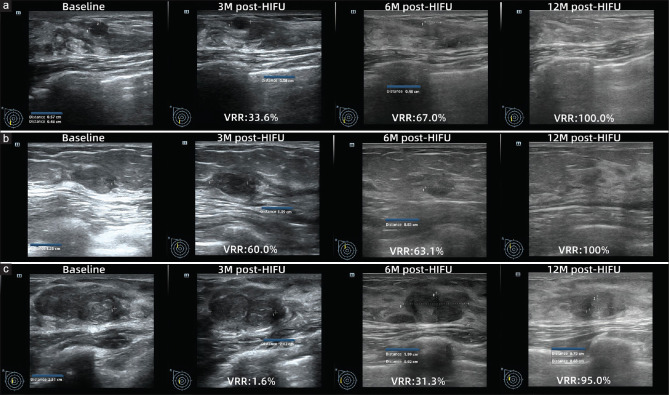

Results: There were 56 FAs ≤10 mm (group 1), 144 FAs with a diameter of 10-20 mm (Group 2), and 45 FAs of 20-30 mm (Group 3). The sonication time of the three groups was 22.5 s, 45.0 s, and 83.0 s (P < 0.05). Based on contrast-enhanced ultrasound evaluation, the median nonperfused volume ratio of the three groups was 74.1%, 87.6%, and 79.2% (P > 0.05), respectively. The volume reduction rates (VRR) of the three groups were 47.3%, 77.0%, and 82.0% at 12 months after HIFU, showing statistical differences. All patients were tolerated well and there were no adverse events after HIFU.

Conclusion: The current evidence indicated HIFU was effective and safe in treating breast FA of different sizes, and the VRR of FA >1 cm at 12 months post-HIFU was greater than that of FA <1 cm.